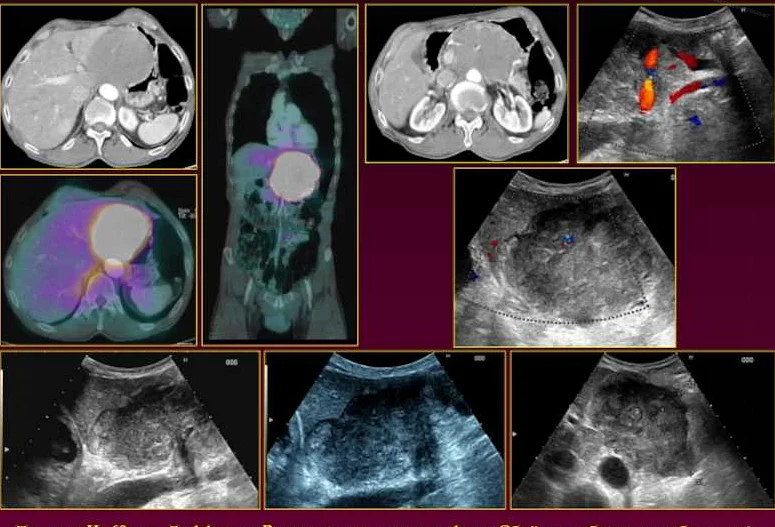

Для дальнейшего уточнения диагноза, установления его стадии, распространенности и характера изменений во внутренних органах используют:

- Рентгенографию органов грудной полости.

- КТ, МРТ (для исследования печени, селезенки, головного мозга, легких, области шеи и др.)

- УЗИ.

- Фиброэзофагогастроскопию (при подозрении на первичные лимфомы либо распространении опухолевого процесса из других органов).

- Радиоизотопное сканирование костей.

- Пункцию с биопсией костного мозга.

диагностический снимок больного лимфомой, на поз. B – результат 3-месячной химиотерапии